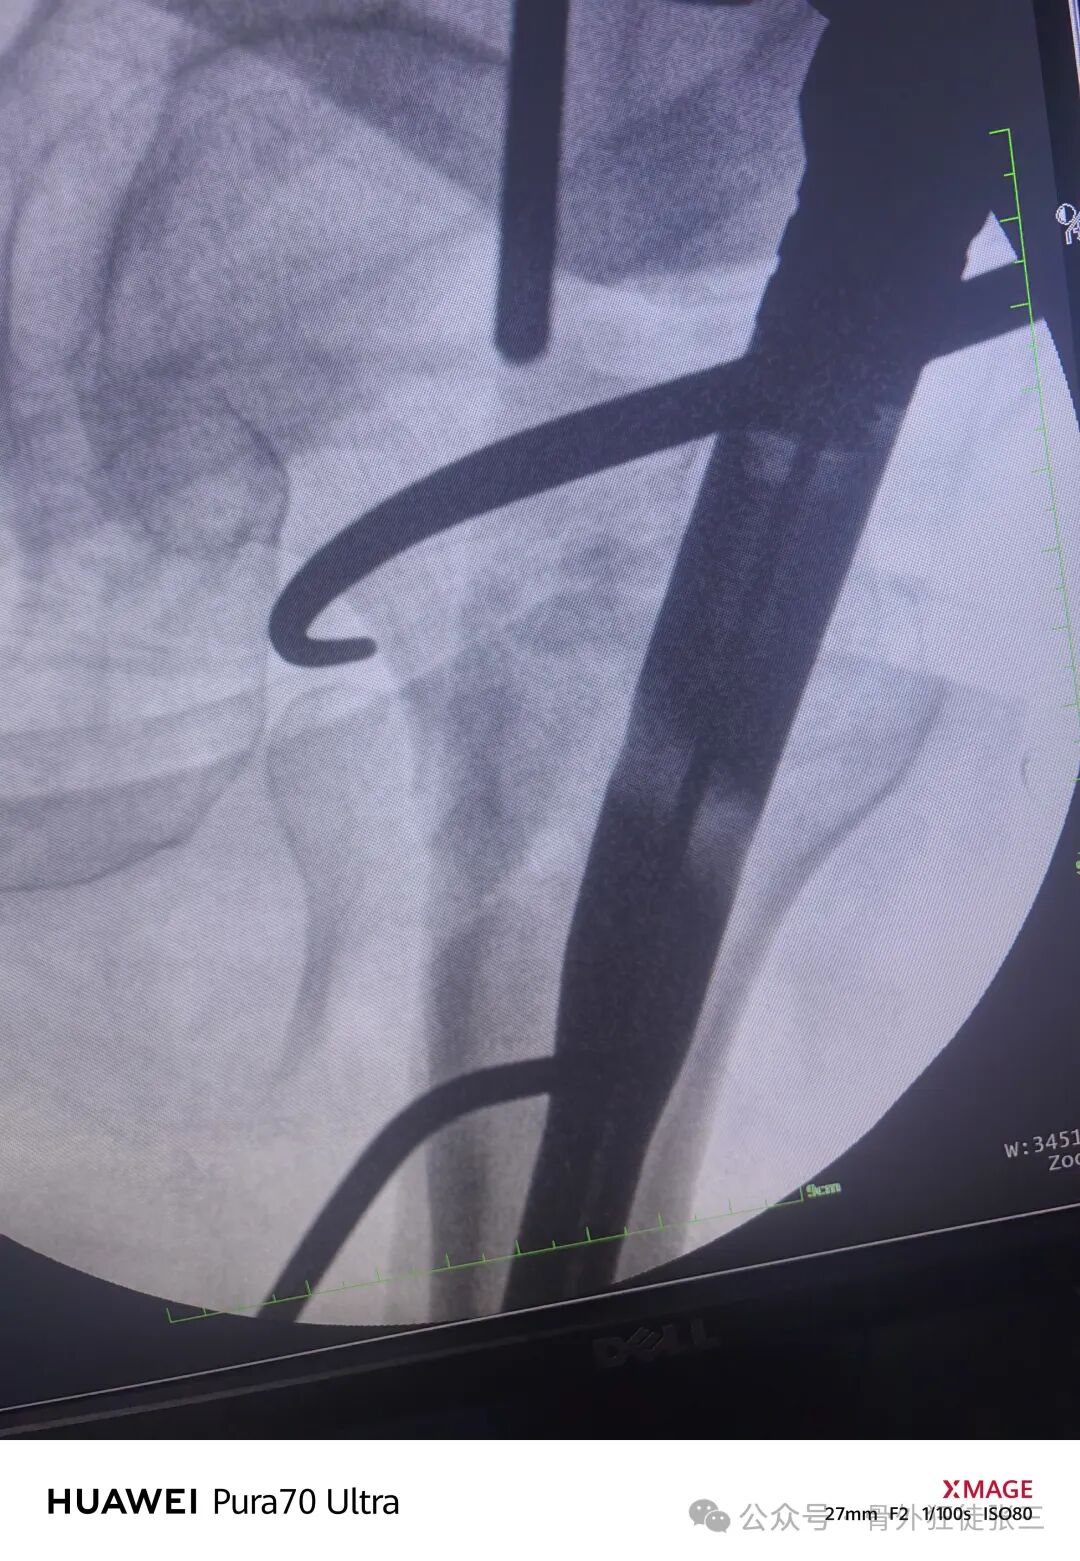

使用微创牵开器

3分钟安装

骨钩从切口入股骨颈复位

再次透视

正位复位满意

导针正位中下1/3

骨钩过牵了

有点阴性支撑

侧位导针居中

远端静态锁定

术中出血约50ml

手术从切皮到缝合

40分钟结束

透视18次